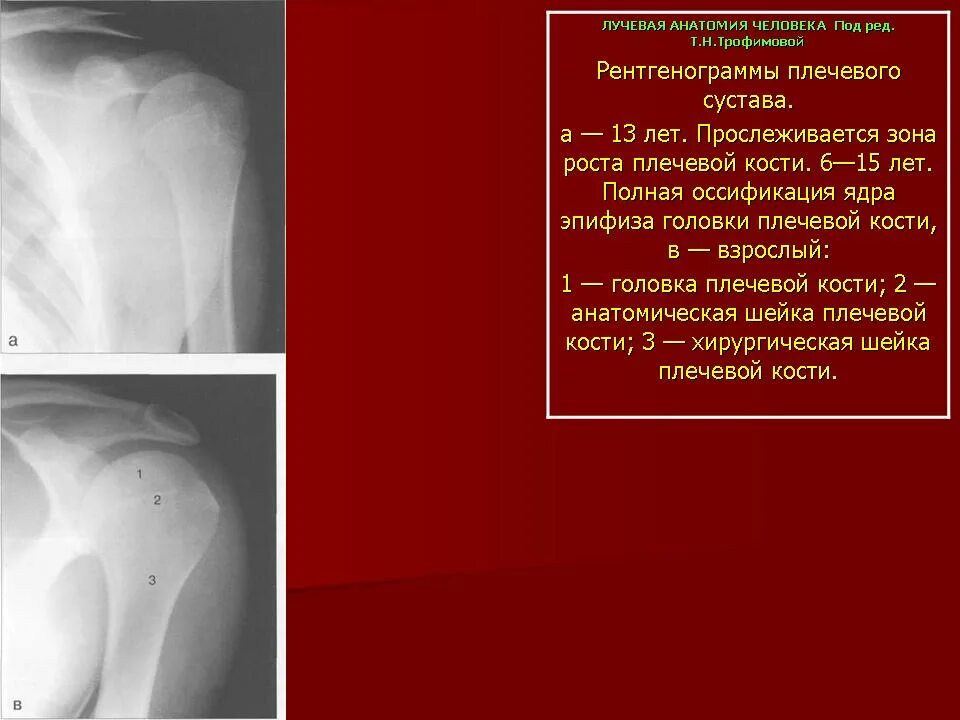

Плечевой сустав у детей